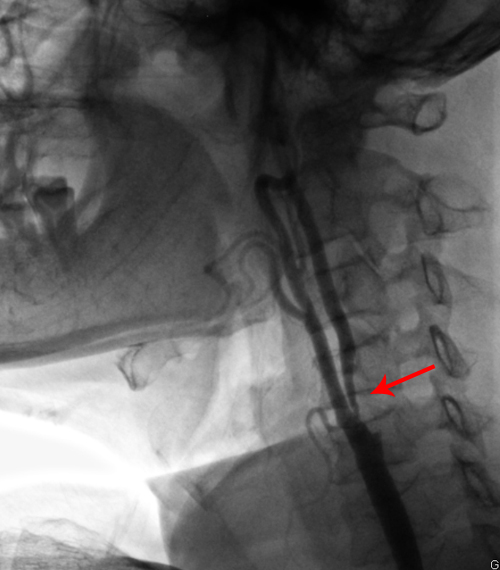

颈CEMRA:双侧颈内动脉起始部节段性狭窄,左侧为著;左侧椎动脉起始部节段性狭窄。